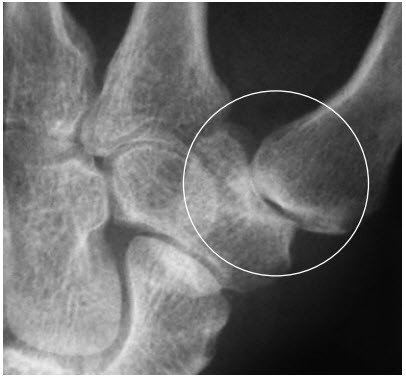

Diagnose

Die Diagnosestellung erfolgt durch gezieltes Befragen des Patienten. Oft fällt bereits beim Anblick des Daumens eine Schwellung der Daumenwurzel auf. Bei der Untersuchung zeigt sich dann eine deutliche Druckempfindlichkeit, die verstärkt wird, wenn der Daumen unter dem Druck durchbewegt wird.